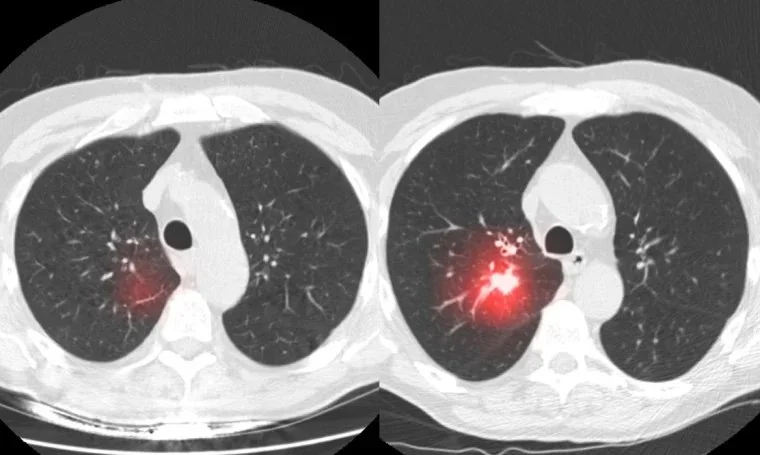

The Future of Lung Cancer Screening — AI, Innovation, and Mobile Healthcare

How AI-driven analysis, improved detection software, and expanding mobile programs are reshaping the future of lung cancer screening.